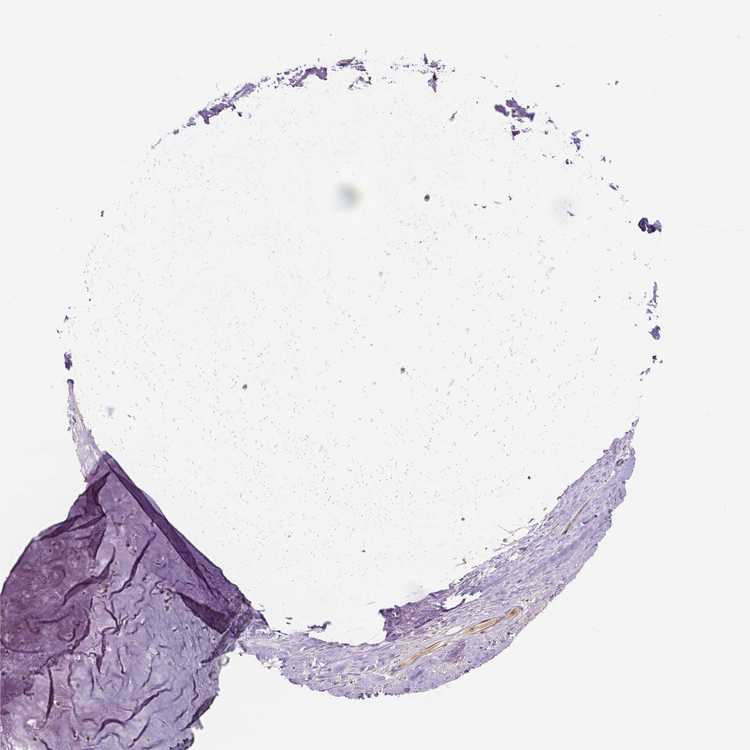

SOFT TISSUE 1 - Antibody stainingi

Antibody staining in the annotated cell types in the current human tissue is reported as not detected, low, medium, or high, based on conventional immunohistochemistry profiling in selected tissues. This score is based on the combination of the staining intensity and fraction of stained cells.

Each image is clickable and will lead to virtual microscopy that enables deeper exploration of all samples and also displays staining intensity scores, fraction scores and subcellular localization as well as patient and tissue information for each sample.

Antibody HPA064687

Chondrocytes Low

Fibroblasts Low